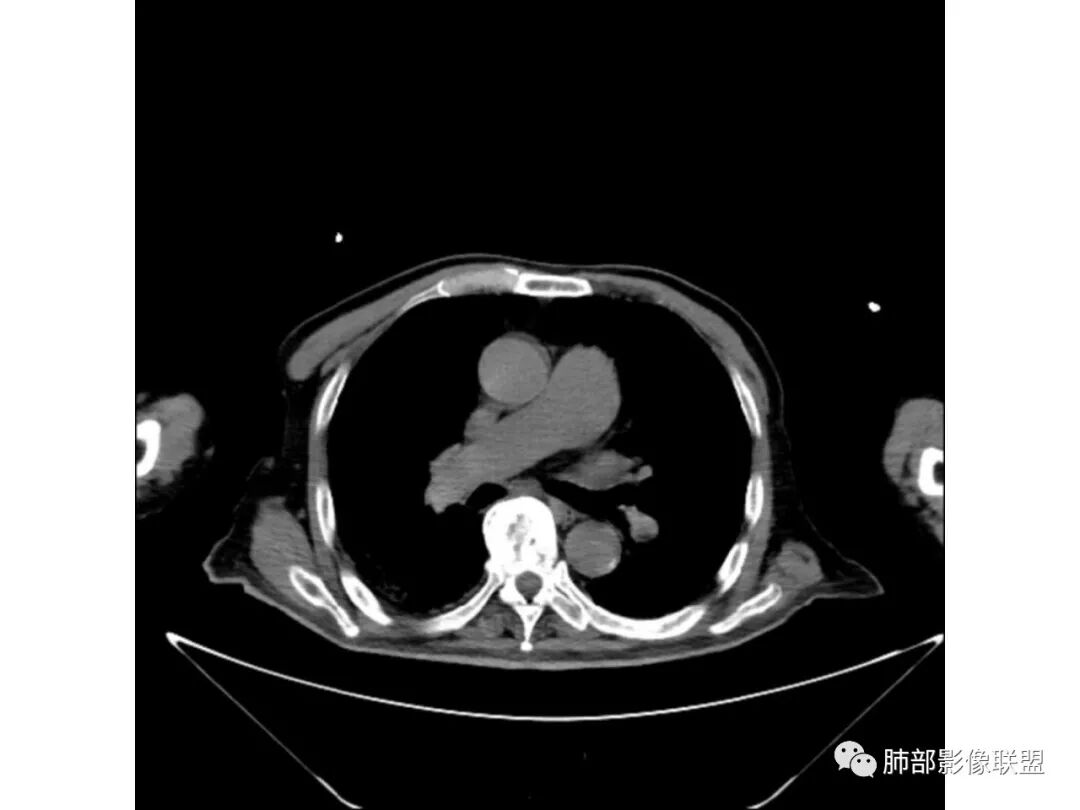

老年男性,既往糖尿病10年,右上肺不均匀实变+两肺实质及间质病变;本例良性感染性病变支持点:糖尿病史+双肺多发的实变,右上肺实变内可见支气管气像;恶性支持点:实变内的支气管似乎呈“枯树枝”样改变,纵隔有超过1.5cm的肿大淋巴结。

个人倾向良性感染性病变>恶性;考虑双肺混合性感染,右肺上叶实变拟结核可能性大,重点鉴别是弥漫浸润性肺腺癌。建议纤支镜检查。

3、增强扫描很重要,增强后,结核的坏死很彻底,很少异常强化,(鳞癌也类同)。而粘液腺癌血管常显影,有时是毛糙的,整体密度偏低,哟其实纵膈窗。

粘液腺癌的很少见纵隔淋巴结肿大,而其他腺癌常见。